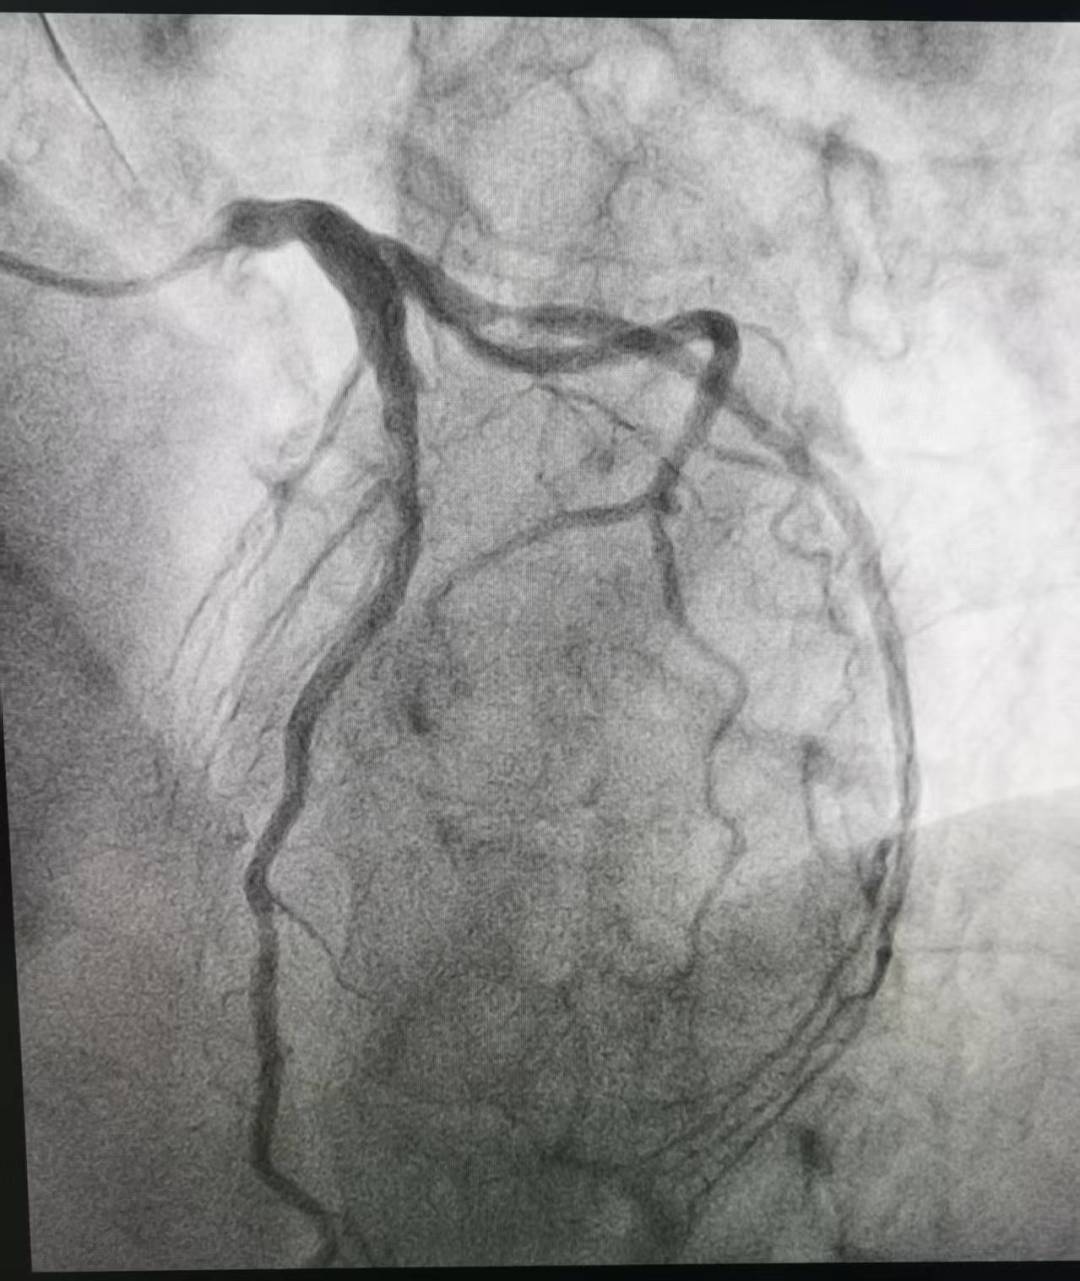

“时间就是心肌,时间就是生命!”心内三科谈金强主任和张用之主治医师立即启动急救绿色通道,为患者急诊行冠状动脉造影(CAG)以明确冠脉病情。造影结果显示:患者对角支自开口处100%闭塞!如此隐蔽的病变,不仅极度考验术者的观察力,更对冠脉解剖结构的熟悉程度提出极致挑战,稍有疏忽便可能漏诊,酿成不可挽回的结果!